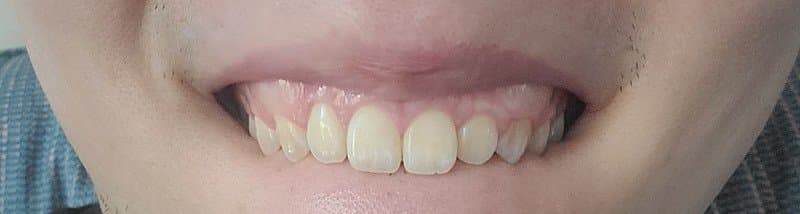

)치아 뼈가 전방으로 많이 나온 상태인가요?

1. 전방으로 많이 나왔다고 볼 수도 있지만 심미적으로 봤을 때 치료를 하지 않아도 되는 정도입니다. 본인이 현재 안모에 불만족스럽다면 이는 치료의 대상입니다.